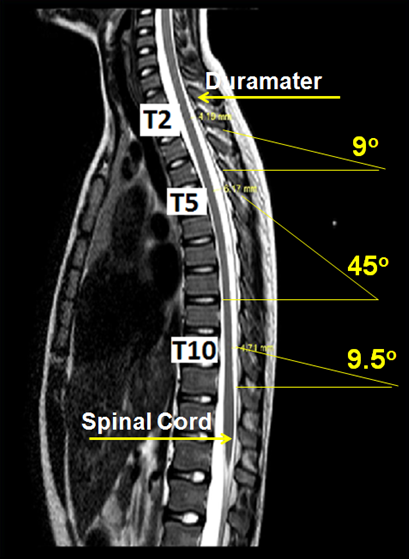

Accidental perforiation of the dura-mater during epidural attempts may happen with an incidence that varies according with to the hability of the professional and the carachteristics of the patient, and it may vary between 0.4% to 4.4% in a series of 6,496 cases, and no patient of the 48 cases with perforation developed neurological sequelae.24–27 An anatomical explanation for the lack of damage was proposed by Imbelloni and Gouveia (Figure 1).28,29 In the printed MNR the following measures where found: 5.19 mm in T2, 7.75 mm in T5 and 5.88 mm in T10, or let us say, suficient distance to permit the careful advancement of a needle (accidentally of intenionally) without reaching the medula and administer anesthetic for a segmental spinal anesthesia.

Figure 1 Magnetic Ressonance Image.

An enquete, among 351 members of the American Society of Neuroradiology, confirmed that mielography in the cervical and thoracic segments is considered safe and continue indicated in some clinical situations.32 Studying the cervical and thoracic column through MRI it is evident that the spinal cord is adhered posteriorly in the cevical region and anteiorly in the thoracic segment.20 The lateral approach between C1 and C2 is point of choice for mielography. This choice can be understood by the presence of a pool of CSF posteriorly and the spinal cord anteriorly. The lateral approach prevents the medula from being touched by the needle. Correcting the distance between the dura-mater and the medula one can see an increase in the distance by the angle of entrance, what reduces the possibility of neurological lesion during the acidental perforation of the dura-mater.